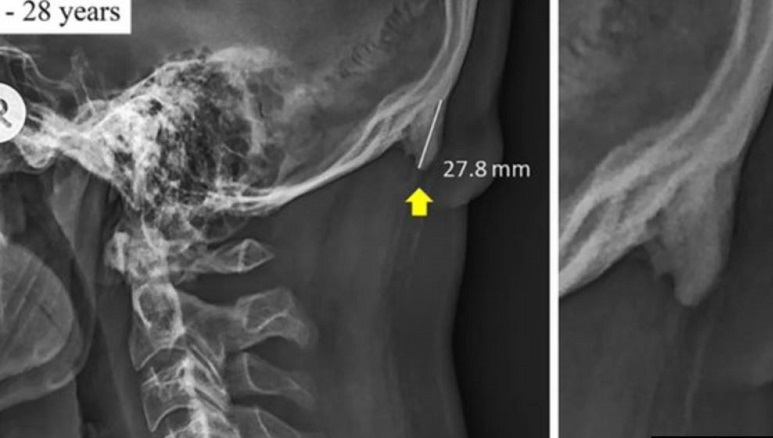

پژوهشگران دانشگاه «سان‌شاین کوست» در «کوئینزلند» استرالیا، شواهدی پیدا کرده اند که نشان می دهد نسل جدید، پشت سرشان، در پائین جمجمه سر درست بالای گردن، برجستگی دارند که بزرگتر و بیرون زده‌تر از نسل های پیشین است. آنها بزرگ بودن این استخوان در جوان‌ها را به طرز قرار گرفتن سر و گردن هنگام استفاده از گوشی تلفن همراه و تبلت مرتبط دانسته‌اند.

به گزارش سایت خبری علمی «ساینس الرت»، این مطالعه بر روی ۱,۲۰۰ تصویر اشعه ایکس از جمجمه سر بزرگسالان استرالیایی انجام گرفت. پژوهشگران دریافتند که ۴۱ درصد از آنهایی که در گروه سنی بین ۱۸ و ۳۰ بودند، این برجستگی استخوانی را داشتند.

این استخوان بیرون زده در برخی تنها ۱۰ میلیمتر بود و زیاد مشخص نبود در حالیکه در برخی دیگر تا ۳۰ سانتیمتر طول داشت.